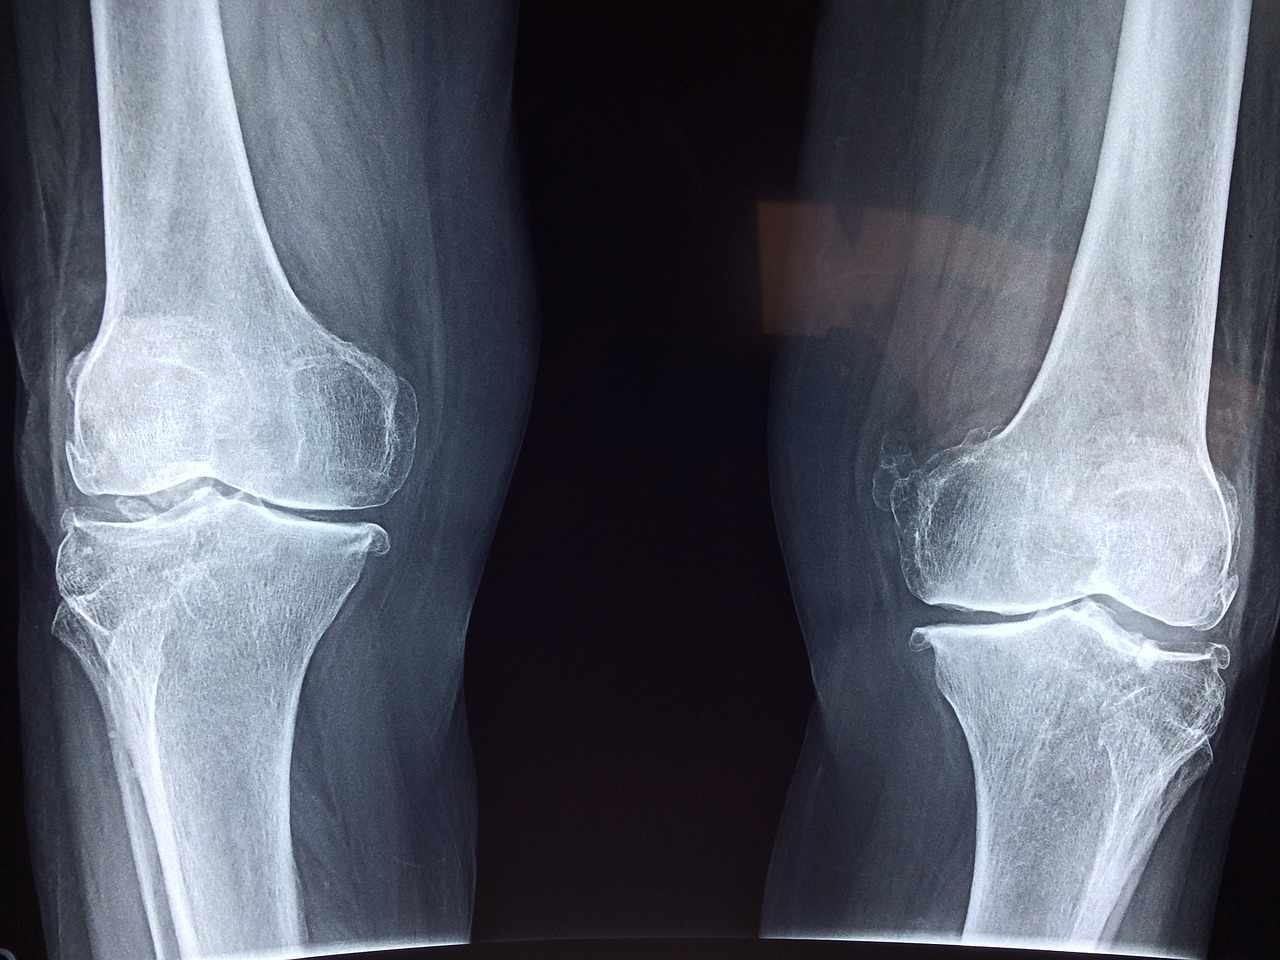

Η τεχνητή νοημοσύνη ανοίγει νέες προοπτικές στον τομέα της ορθοπεδικής χειρουργικής καθώς μπορεί να βοηθήσει τους γιατρούς να προσαρμόσουν τις στρατηγικές αποκατάστασης σύμφωνα με τις ανάγκες του εκάστοτε ασθενούς.

Ερευνητές στις ΗΠΑ εφάρμοσαν τεχνικές τεχνητής νοημοσύνης προκειμένου να κατανοήσουν τον αντίκτυπο που μπορεί να έχει ένα κάταγμα στην υγεία ενός ασθενούς και να σχεδιάσουν τις κατάλληλες στρατηγικές αποκατάστασης. Η ανάλυση των μοτίβων βάδισης στην πρώιμη φάση μετά τον τραυματισμό προσφέρει πολύτιμες πληροφορίες σχετικά με τον αντίκτυπο που έχει το γεγονός στη βάδιση και την αποκατάσταση του ασθενούς.

Η νέα μελέτη αποκάλυψε σημαντική συσχέτιση μεταξύ των ποσοστών επανεισαγωγής στο νοσοκομείο μετά από χειρουργική επέμβαση κατάγματος και της παρουσίας υποκείμενων ιατρικών καταστάσεων. Αν και προηγούμενες μελέτες είχαν εντοπίσει συσχετίσεις μεταξύ αυτών των ιατρικών καταστάσεων και των ορθοπεδικών επιπλοκών, οι συσχετίσεις αυτές δεν θεωρούνταν στατιστικά σημαντικές.

«Τα ευρήματά μας καταδεικνύουν το βαθύ αντίκτυπο που μπορεί να έχει η ενσωμάτωση της μηχανικής μάθησης και της ανάλυσης βάδισης στην ορθοπεδική πρακτική, όχι μόνο στη βελτίωση της ακρίβειας των προβλέψεων των επιπλοκών μετά τον τραυματισμό, αλλά και στην προσαρμογή των στρατηγικών αποκατάστασης στις ατομικές ανάγκες των ασθενών», δήλωσε ο επικεφαλής συγγραφέας της μελέτης Μοσταφά Ρεζαπούρ από την Ιατρική Σχολή του Πανεπιστημίου Wake Forest.

«Η προσέγγιση αυτή αντιπροσωπεύει μια καίρια στροφή προς μια πιο εξατομικευμένη, προγνωστική και τελικά πιο αποτελεσματική ορθοπεδική φροντίδα» πρόσθεσε.

Ο Δρ. Ρεζαπούρ πρόσθεσε ότι η μελέτη υπογραμμίζει την κρίσιμη σημασία της υιοθέτησης μιας ολιστικής θεώρησης που περιλαμβάνει όχι μόνο τις μηχανικές πτυχές της αποκατάστασης των τραυματισμών αλλά και το ευρύτερο φάσμα της υγείας του ασθενούς.

«Πρόκειται για ένα βήμα προς τα εμπρός στην προσπάθειά μας να βελτιστοποιήσουμε τις στρατηγικές αποκατάστασης, να μειώσουμε τους χρόνους ανάρρωσης και να βελτιώσουμε τη συνολική ποιότητα ζωής των ασθενών με κατάγματα των κάτω άκρων», δήλωσε.